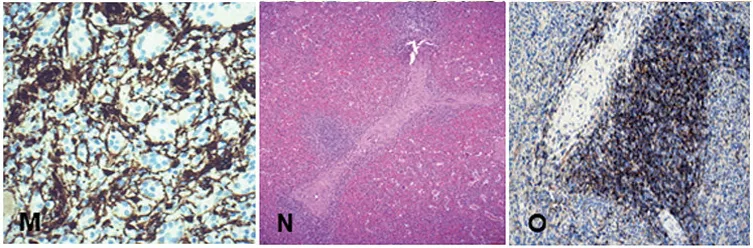

Figure1GtoM, red pulp;

Figure1NandO, showingTzone.N, periarteriolar lymphoid sheath, surrounded by lymphocytes

Figure1OCD4Shows helperTcells.